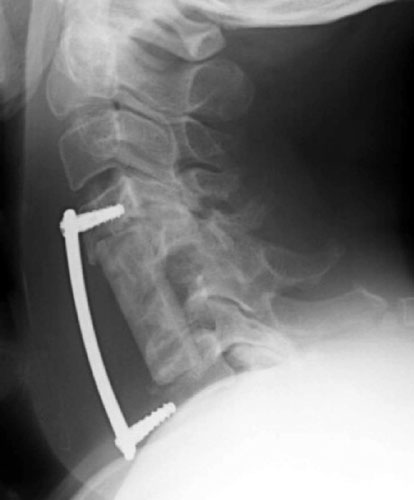

This is lateral radiograph taken several hours AFTER the incident with the food truck. Note the distal end of the fixation plate has loosened and is nearly completely out. The distal screws have minimal purchase in the C7 vertebral body.